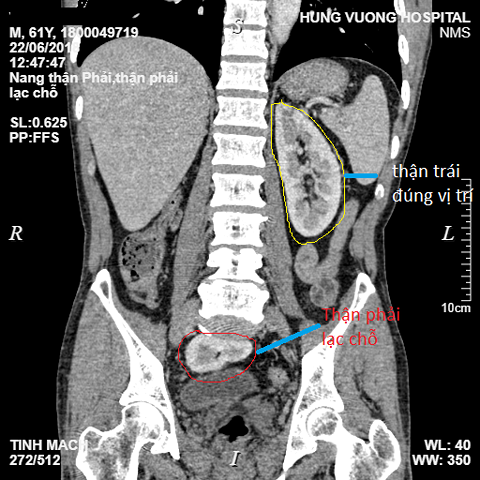

Theo người nhà, bệnh nhân đau bụng âm ỉ kéo dài nhiều tháng nay. Gần đây, tình trạng đau bụng ngày càng tăng nên vào viện khám. Kết quả chụp CT cho thấy, có hình ảnh nang nhỏ thận phải, đặc biệt thận phải nằm lạc chỗ trong tiểu khung. Bác sĩ chẩn đoán bệnh nhân bị nang thận phải, thận phải lạc chỗ và cần phẫu thuật cố định thận phải.

| Quả thận phải đi lạc xuống vị trí tiểu khung, Ảnh: Infornet |